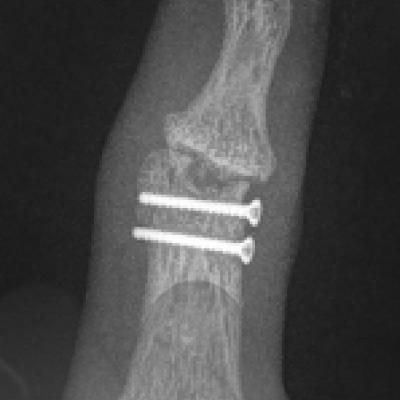

Arthrodesis

This is the technique of fusing the joint in a position of best function that is appropriate to each individual patient. This is a very durable and reliable way of relieving pain and correcting severe deformity although it does prevent any movement of the affected joint from the fused position. It has been a technique employed since the early 1900’s with good long term results. It is particularly useful in younger patients with a requirement for heavy manual activity and commonly used to treat arthritis in the smaller joints of the fingers such as the DIP joints but can be performed in almost any joint. Risks of surgery include a failure to fuse the joint causing ongoing pain, risk of implant breakage or irritation to surrounding tissues, injury to surrounding structures including skin, nerves, blood vessels and cells that produce the nail and can also be complicated by infection.